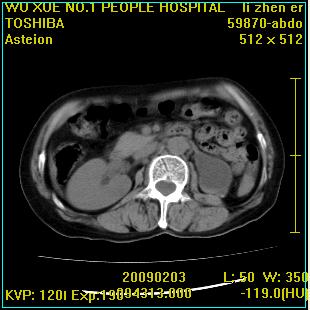

标题: CT18564:女,57岁,无不适,体验B超提示肾积水等 [打印本页]

标题: CT18564:女,57岁,无不适,体验B超提示肾积水等

左肾及左输尿管上端结石,左肾重度积水并左肾萎缩(不排除左肾先天性发育不良)。

左输尿管上端结石,左发育不良性多囊肾并积水;

右肾代偿性增大并肾盂积水,脾大。

左肾及左输尿管上端结石,基本上丧失肾功能了。

此患都左肾呈囊性变,边缘有高密度钙化,还是考虑结核吧.